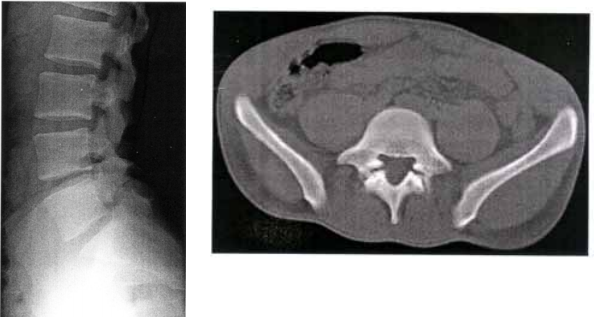

70 19 歲男性病人主訴下背痛。圖為本次就診之腰椎 X 光攝影及電腦斷層掃描。最可能的病變部位為何?

(A) Pedicle (B) Pars interarticularis (C) Facet joint (D) Lamina